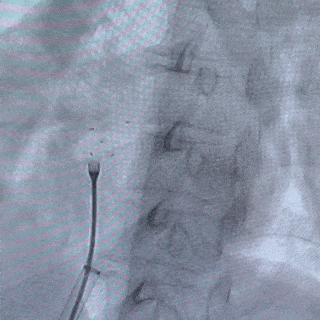

成型锁定

鞘管抵住封堵器后,前顶钢缆并固定,牵拉成型线锁定

牵拉试验

牵拉试验时,5个Mark点一起摆动,相对位置未发生明显变化,表明已成功锁定

释放封堵器

释放封堵器前,再次牵拉成型线锁定

撤出成型线后,前抵鞘管,逆时针旋转钢缆,5个Mark点相对位置不变,封堵器释放成功

释放后影像

最后封堵器盘面稳固扣合,形态扁平且位置良好,封堵成功